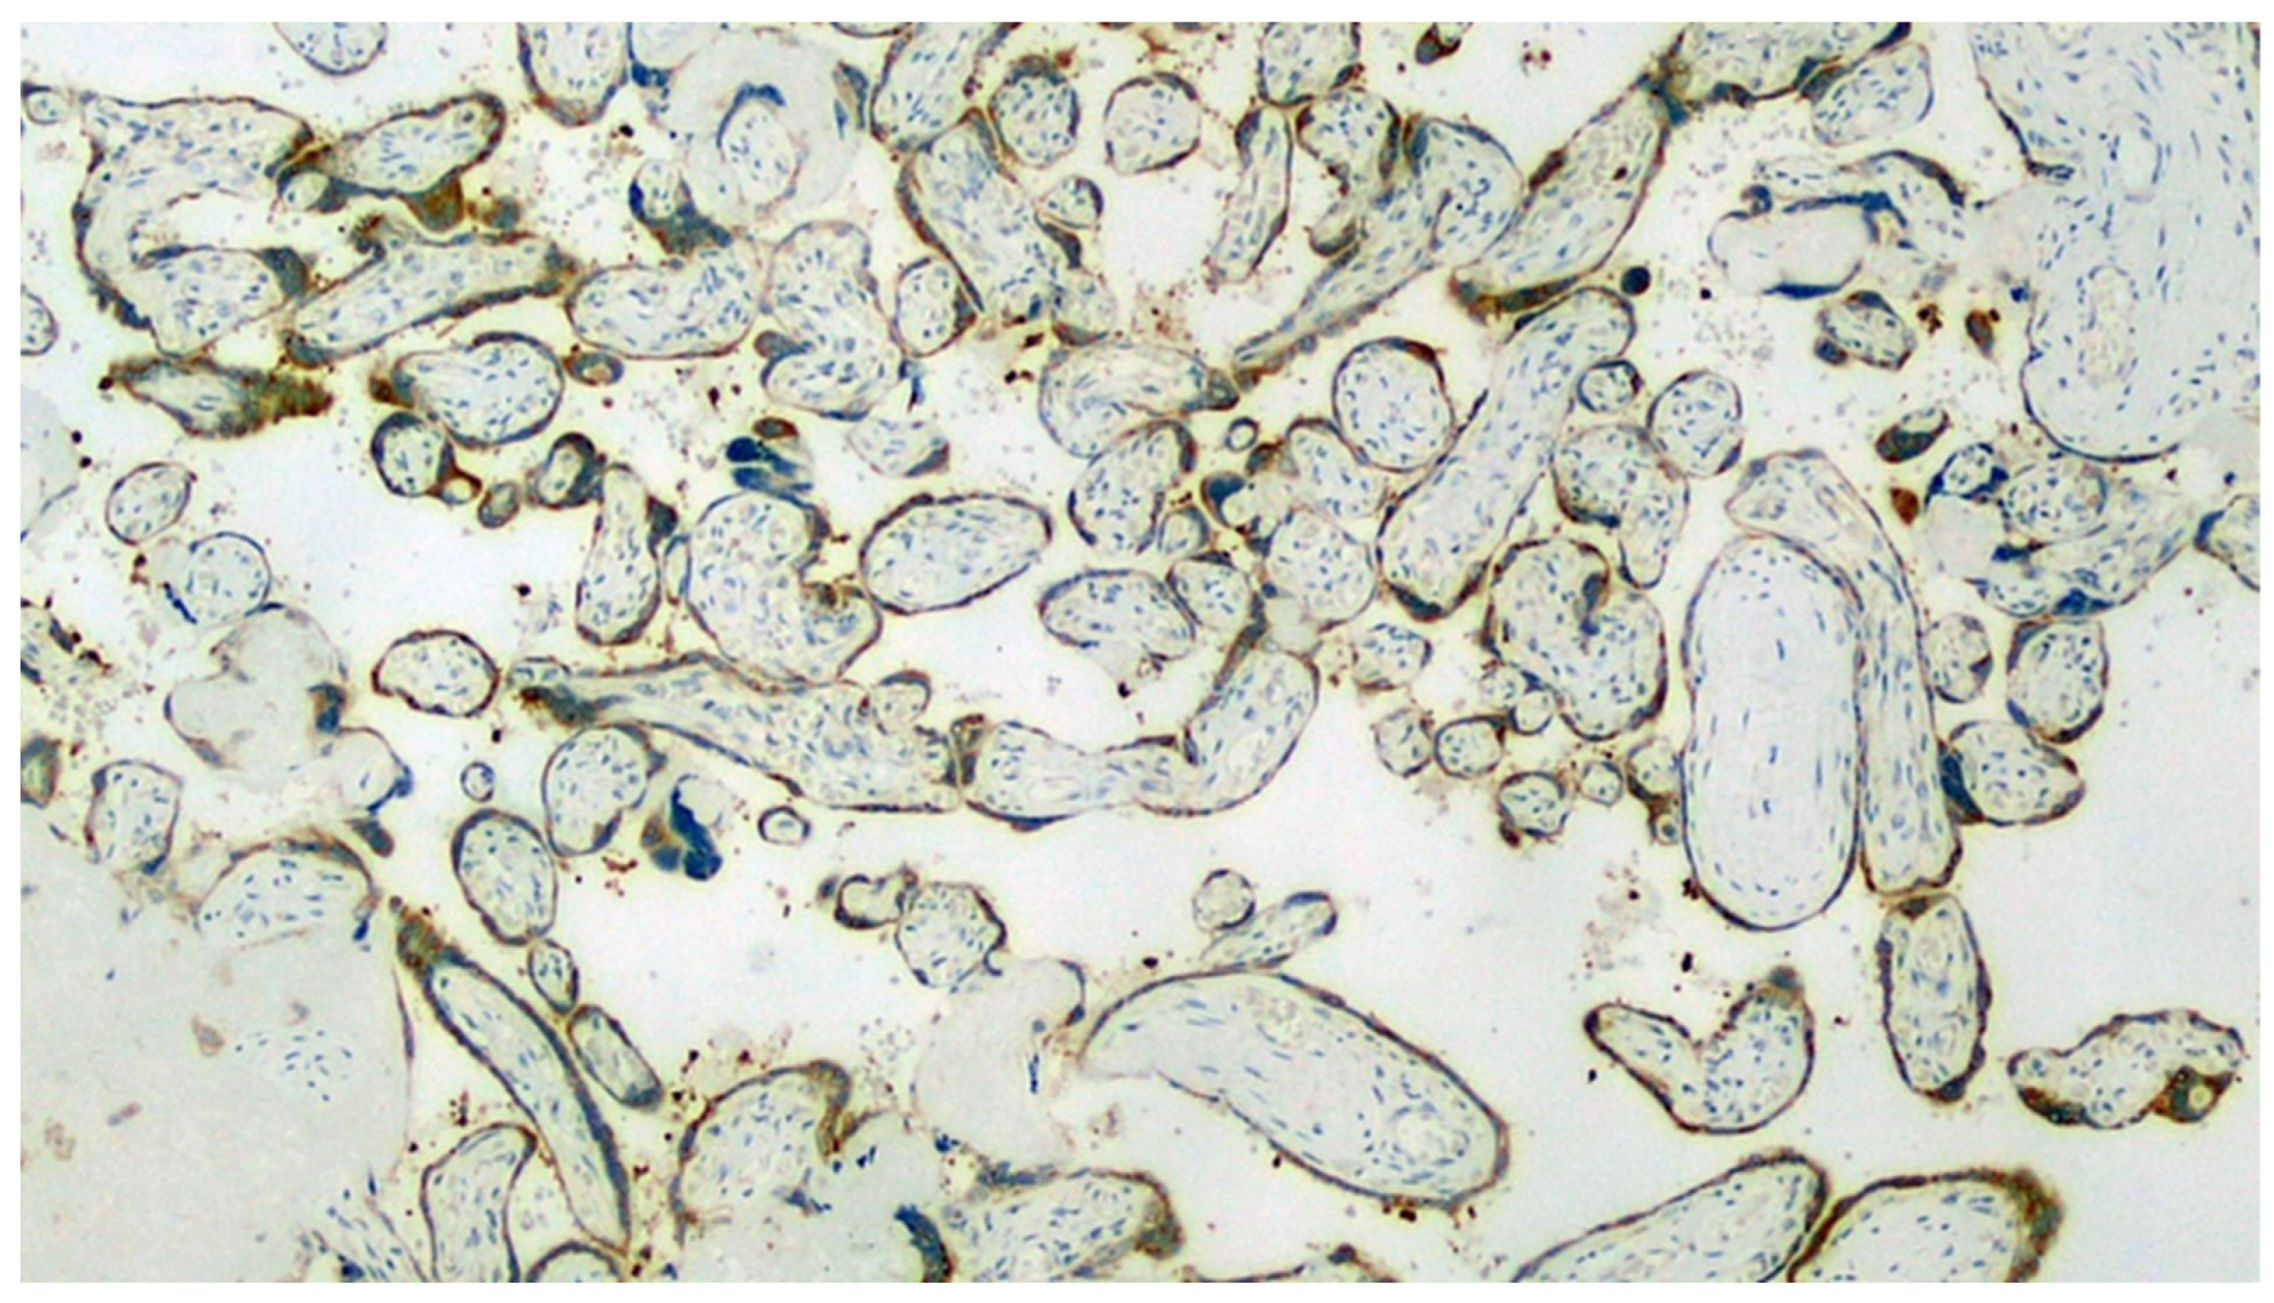

Figure 6.

Section set up for immunohistochemistry investigation using the Sars-CoV-2 anti-spikes glycoprotein antibody. Note the widespread involvement of brown-colored syncytiotrophoblast (Immunohistochemistry, IHC, 100×).

Figure 7.

Detail of the previous image. In addition to the positivity expressed by the trophoblast, a very intense positivity is observed in the leukocytes of the maternal blood (IHC, 400×).